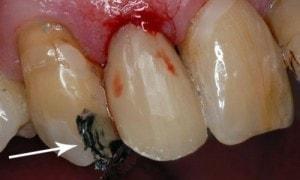

Caries in incisor teeth

Decay in teeth #'s 7, 8, and 10

Immediate objective is to manage the more serious cavities, and then address periodontal issues.

#’s 7 & 8 completed

Arrow shows a distal area which needs to be shaped better. When patient returns I will improve on the contour with a #15 blade.